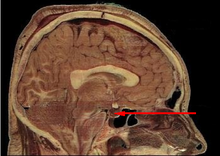

Lage der Hypophyse (Pfeil)